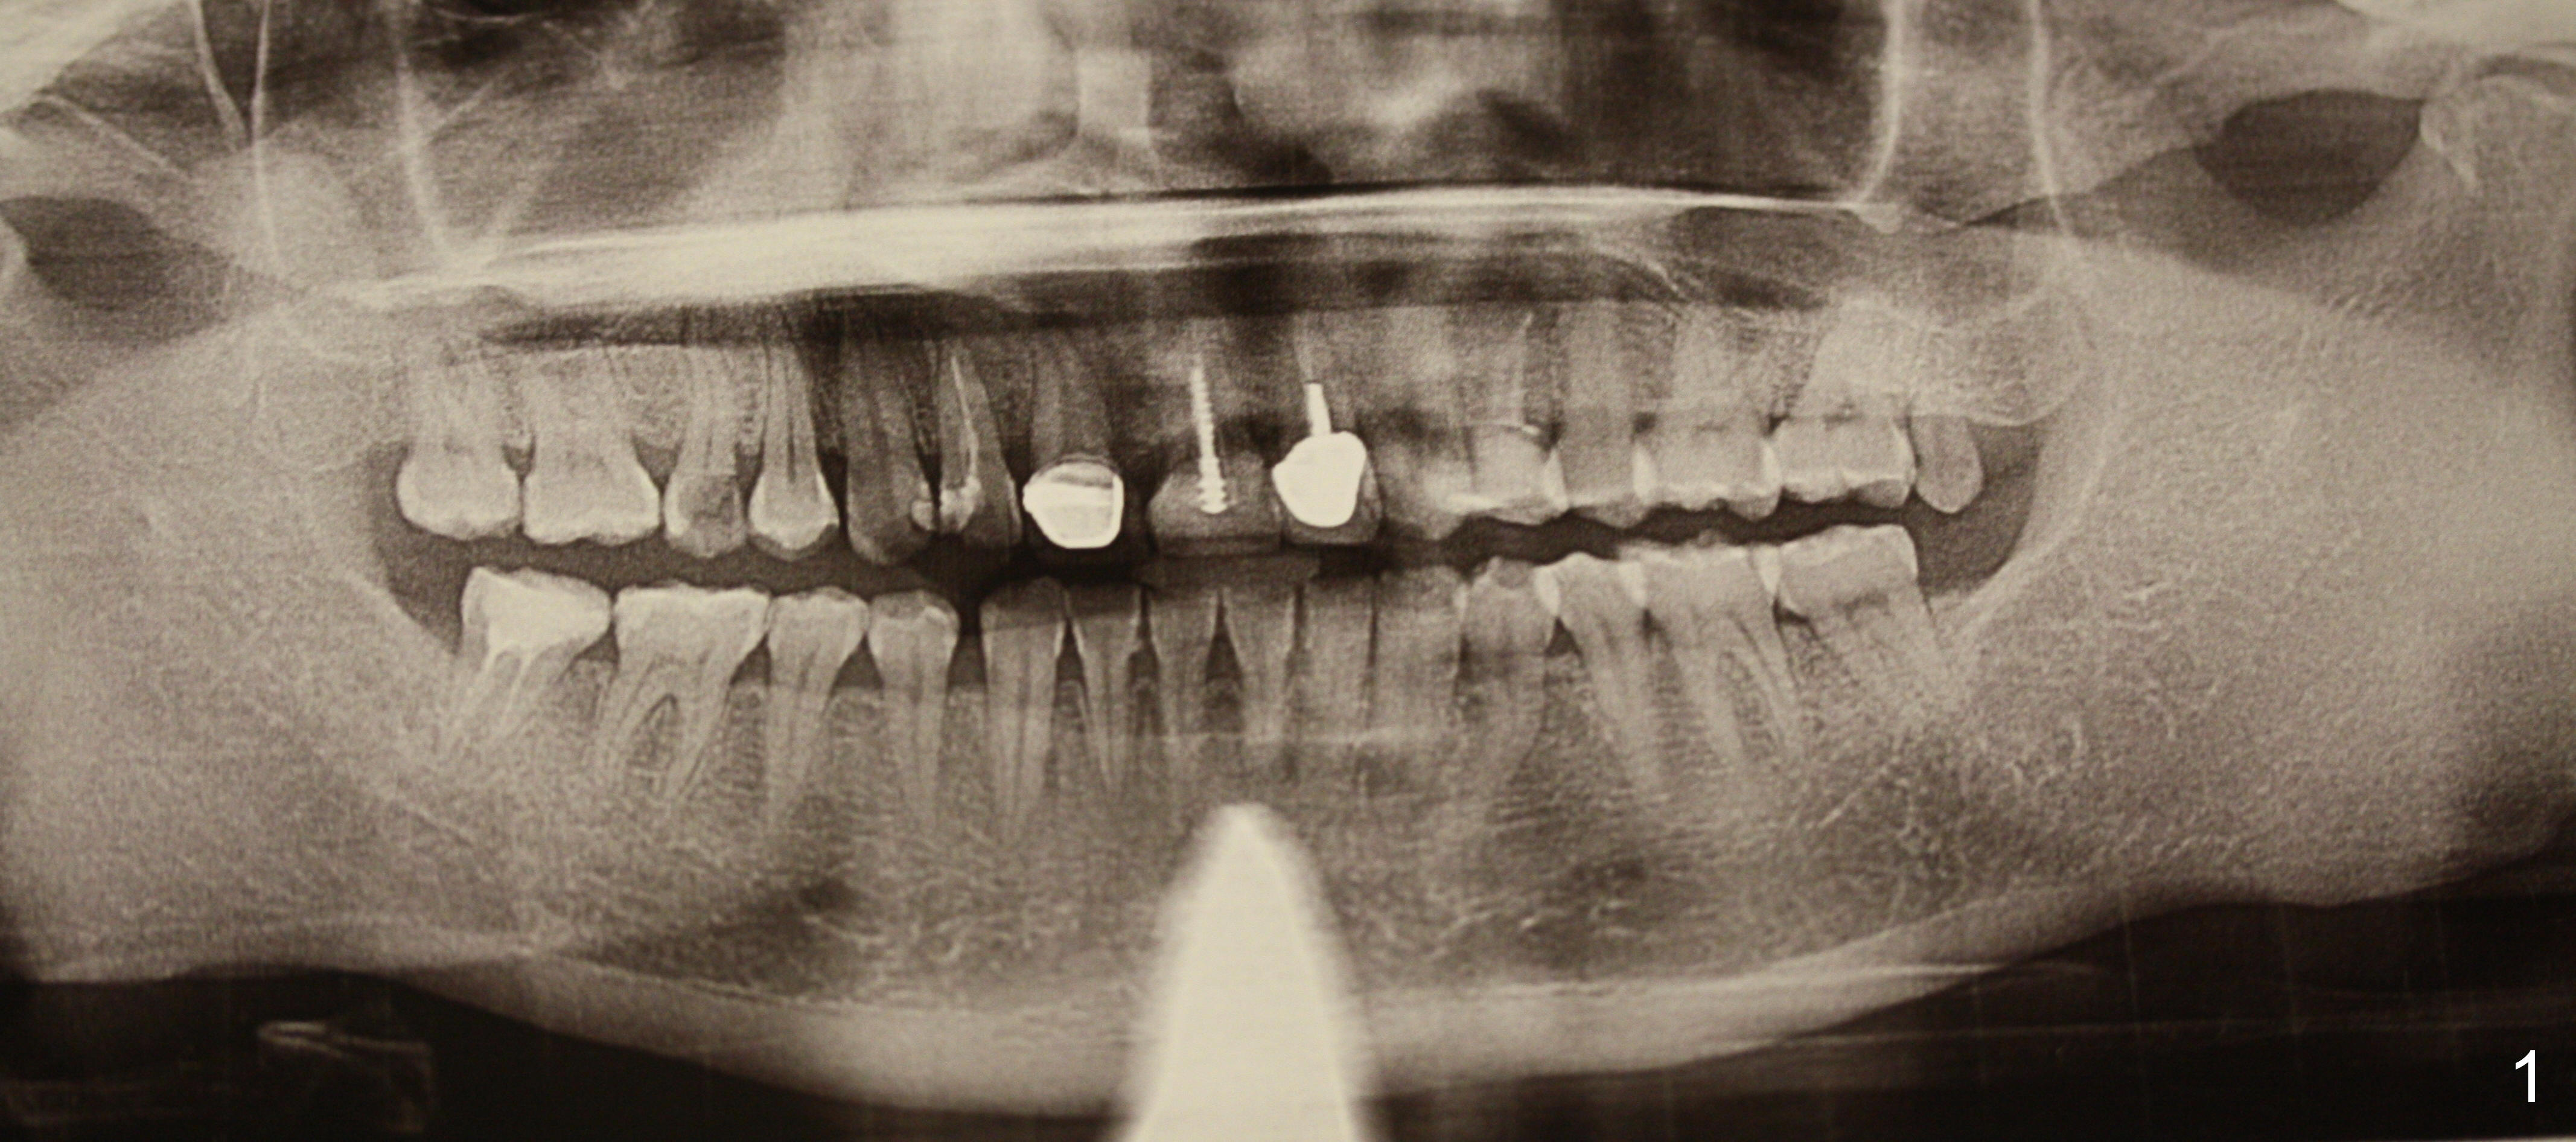

A 40-year-old lady has multiple restorations (Fig.1). Two of them require implants (#4 (Fig.2, severe caries) and #8 (Fig.3, root fracture).  The root of #4 is long and curved (Fig.2).  It may present a challenge to extraction, but not implant placement.  The narrow and long root is favorable to primary stability.  A 2 mm pilot drill is used to initiate osteotomy in the palatal wall of the socket, followed by 2.5 and 3 mm reamers at 17 mm (gingival level).  If the bone is soft, the depth for the 3 mm reamer will be reduced to 14 mm.  A 4.5x20 mm Tatum tapered tap will be used at 17 mm deep to test stability.

If the stability is good, a bone-level implant will be placed.  How long is the implant?  Why do we not use a tap from the bone-level implant kit?